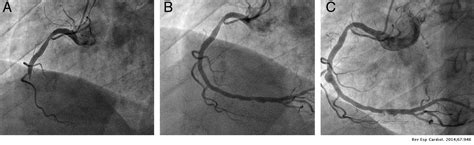

Hallazgos Ecocardiográficos Iniciales

La ecocardiografía inicial reveló:

- Ectasia de ambas arterias coronarias principales.

- La arteria coronaria derecha mide 2,2 mm con hiperrefringencia de paredes.

- La arteria coronaria izquierda mide 2,5 mm con una dilatación más distal en la descendente anterior de 3,5 mm.

Una nueva ecocardiografía realizada dos semanas después mostró una progresión significativa de la condición.

Desarrollo de Aneurismas Coronarios Gigantes

La ecocardiografía de control a las 2 semanas demostró el desarrollo de aneurismas coronarios gigantes, alcanzando un tamaño de 8 mm.

| Variable | Valor Inicial | Valor a las 2 Semanas |

|---|---|---|

| Arteria Coronaria Derecha | 2,2 mm | 8 mm (Aneurisma) |

| Arteria Coronaria Izquierda | 2,5 mm (Dilatación distal de 3,5 mm) | 8 mm (Aneurisma) |